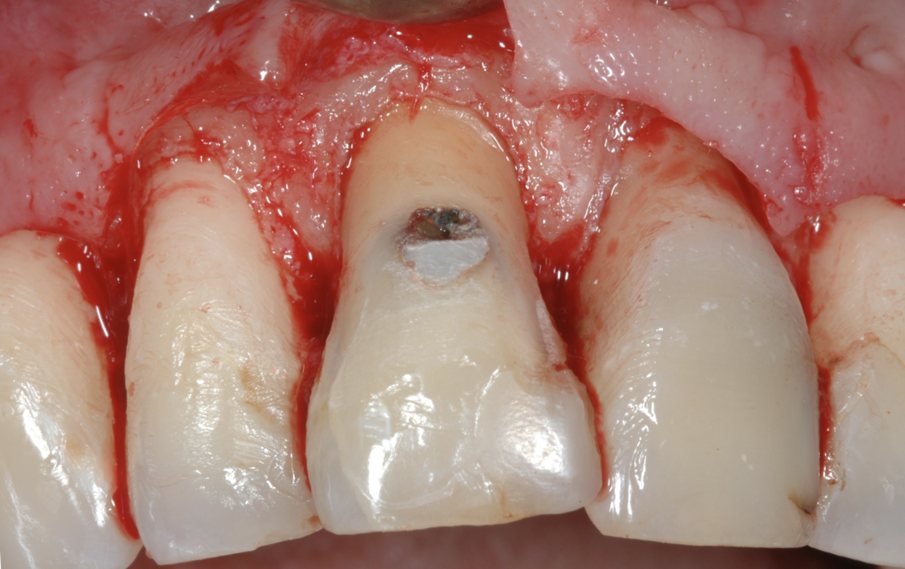

Fig. 4 - Il disegno del lembo chirurgico, sollevato solo sull’aspetto buccale.

Fig. 5 - Il rapporto tra lesione cariosa e tessuto osseo di sostegno appena sollevato il lembo.

Fig. 6 - La distanza ottenuta tra lesione cariosa e tessuto osseo di circa 3 mm al termine dell’osteo-plastica e ostectomia in prossimità dell’11, con una leggera riduzione in senso buccale della sporgenza della radice.